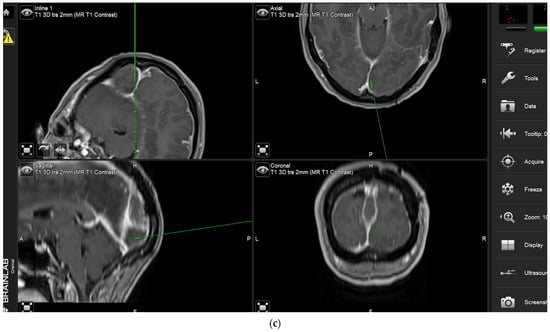

The aim of fluorescence assessment and tissue biopsy in bulk tumor is to determine whether a tumor shows fluorescence and to correlate fluorescence with tumor histology. To collect this biopsy, surgeons are asked to switch to blue light as soon as bulk tumor is encountered during surgery, to determine whether any fluorescence is visible and to take a biopsy from a fluorescing part of the tumor. A neuronavigation screenshot is taken from the exact location of the biopsy (Figure 1). The entire sequence is recorded using the microscope’s video system.

During the course of conventional white light surgery, the surgeon might encounter tissue which appears uncertain. From such “indeterminate” tissue the surgeon might require more information based on fluorescence. In such cases, the observation of fluorescence might lead to a change in surgical decision or surgical strategy. Such instances of indeterminate tissue may be found at the dural tail, in scar tissue with cases of recurrent meningioma, in the bone flap or at bony resection margins. In cases in which the surgeon requires more information based on fluorescence, the region in question is marked by the navigation pointer and a screenshot is taken. At this stage, the surgeon records his presumed diagnosis for the tissue area he or she desires more information for (“likely” or “unlikely” tumor) and his surgical decision based on his impression under white light (to resect or not to resect). The surgeon then switches to blue light, records whether he or she sees fluorescence, and states whether he or she plans to change surgical strategy based on fluorescence status. Under white light, the uncertain tissue is then biopsied for later histological evaluation. The entire process is recorded using the microscope’s video camera for later assessment by the review panel (Figure 2).

After clearing a field from tumor under white light, with the surgeon no longer being able to identify residual tumor in that field of view, the surgeon has the possibility of switching to blue light to determine whether any pathological tissue can be identified based on fluorescence. If the surgeon finds residual fluorescing tissue after switching to blue light, this area is pointed out using the neuronavigation pointer (and a navigation screenshot is taken). A biopsy is taken from the exact same region after switching back to white light if this can be performed safely. This procedure is also recorded by video from beginning to end. Such interrogations might be performed at multiple stages of surgery, provided a particular area (field of view) has been cleared of tumor according to the impression of the surgeon under white light. The interrogation of an inconspicuous bone flap also constitutes an “end of surgery” scenario if the surgeon wants to rule out any tumor infiltration in the bone. If any fluorescent bone is encountered, then this is biopsied prior to drilling of the bone flap (Figure 3).

Study reviewers are supplied with various segments of the videos acquired during surgery in a random order, with video segments from a single case not being reviewed en bloc by a single reviewer but rather being split and distributed among reviewers. Regarding additional data, reviewers are acquainted with the patient’s age, whether the patient has a recurrent or de novo tumor, the orientation of the patient in space, and, for each segment, the neuronavigation screenshot correlating with the video segment or any biopsies.